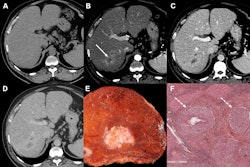

Images in a 55-year-old patient show hepatitis C-related cirrhosis and a transjugular intrahepatic portosystemic shunt (dashed arrow), with an undiagnosed tumor (dashed circle) at pretransplant imaging by both readers. Left: Noncontrast-enhanced axial CT image with a treated observation (dashed circles on the left, middle, and right images) and dense lipiodol staining (arrows) in the anterior right liver. Middle: Late arterial phase CT image with no appreciable enhancement. Right: Delayed phase image with no appreciable washout. The lesion was deemed at explant pathology to have 20% necrosis. Image courtesy of RSNA.